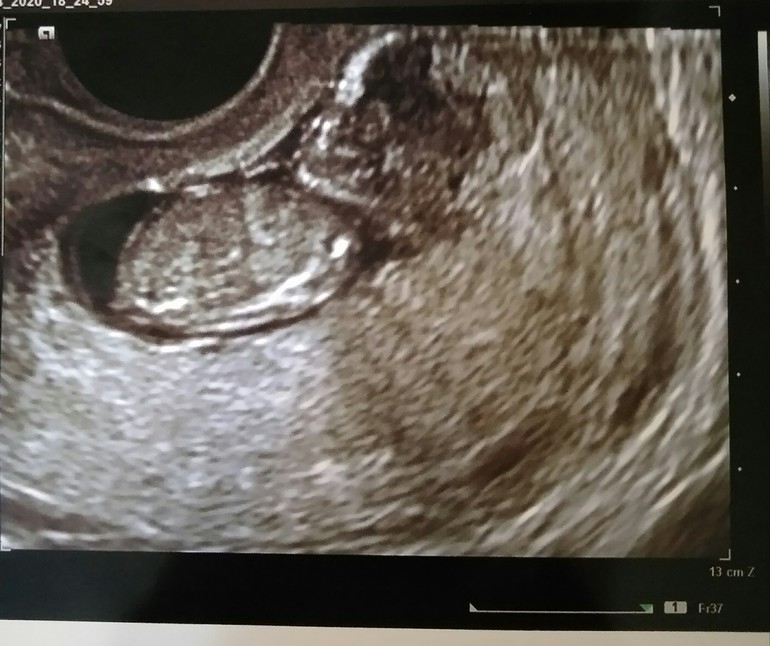

Гадаем пол на 12 неделе фото (+параметры)

У меня три мальчика и девочка , всех сразу определили на первом скрининге . Поэтому не только мальчиков видно сразу) да и на 4 ребенке я уже сама определила легко пол) у мальчиков половой бугорок у меня как у вас на снимке, чуть под наклоном и неровный. У девочки даже загибается немного в сторону позвоночника и ровный. Хотя шанс конечно есть всегда,100 процентов в 11 недель никто не даст) Поэтому на девочку у вас тоже есть шанс) отпишитесь потом кто окажется)

Мне кажется это мальчик(вам же мальчика по Узи сказали?) Вот мальчик на таком же сроке У девочек половой бугорок более параллельный и ровный

У малыша половой бугорок не параллелен позвоночнику, а как бы чуть под наклоном. Но при этом и не торчит однозначно вверх. Поэтому непонятно точно, мальчик или девочка 🤔 Возможно, с нижнего ракурса там было видно что-то, что не видно тут. В любом случае рановато для точного определения пола, не настраивайтесь пока на конкретный пол. А так узисты бывают очень рукастые, да - у меня племянник до 30 с лишним недель был 100% девочка, а потом вдруг отросло, видимо 😄